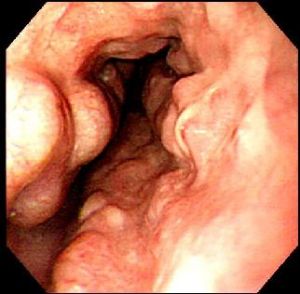

食管靜脈瘤呈青藍色或紫藍色圓形或卵圓形扁平狀隆起,表面黏膜完好,無新近或陳舊性出血灶,無搏動,邊界清楚,如無食管合併症,則周圍食管黏膜無異常;如靜脈瘤為多發性,則各個靜脈瘤之間有正常食管黏膜間隔而非連續性;如與食管靜脈曲張並存,其間也間隔有正常食管黏膜;食管靜脈瘤無出血、潰瘍、癌變等,也不引起食管解剖或功能性狹窄,屬良性病變。

一般使用內鏡診察,此外還可進行CT診察、超聲內鏡診察(Endoscopicultrasonography:EUS),以觀察其引起出血的可能性、詳細狀態、判斷治療效果等。通過內鏡診察來觀察食管靜脈瘤的出血、糜爛以及周圍的血管等,並以此決定治療方針。